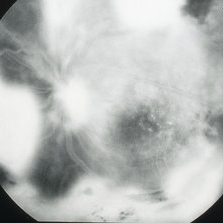

Mid-phase fluorescein angiogram frame of the left eye of a 23-year-old Vietnamese female with Eales Disease showing multiple areas of NVE and areas of capillary loss and nonperfusion OS.

Imaging device: Topcon VT-50

Condition/keywords: Eales disease, FA mid phase, fluorescein angiogram (FA), neovascularization elsewhere (NVE)